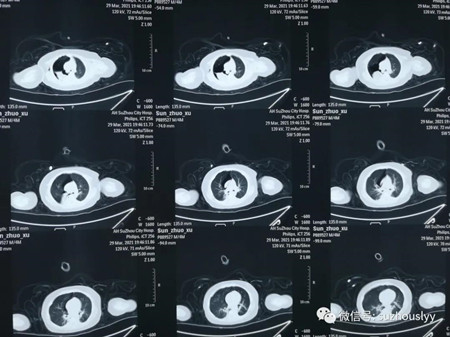

呼吸机通气支持下,患儿仍然显著呼吸困难,氧饱和度不能维持正常水平,而且持续发热,精神反应极差。急查CT发现:两肺严重感染,大量气胸,右上叶肺实变。

急救团队紧急为患儿实施了胸腔穿刺排气术,患儿呼吸困难稍有好转,氧饱和度开始回升,但严重而又复杂的肺部病变仍然时刻在威胁孩子的生命。经紧急、反复、慎重讨论,并征得家属理解同意后,决定为孩子实施支气管镜急诊诊疗术。